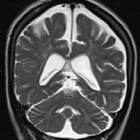

Magnetic

Resonace Imaging findings in a case of infantile Refsum disease. Axial and coronal (c-d) T2-weighted images confirm white matter changes in the supratentorial periventricular areas and in the cerebellum.